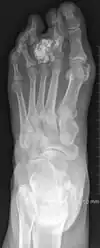

| Non-cancerous | Subungal exostosis[2] |

|